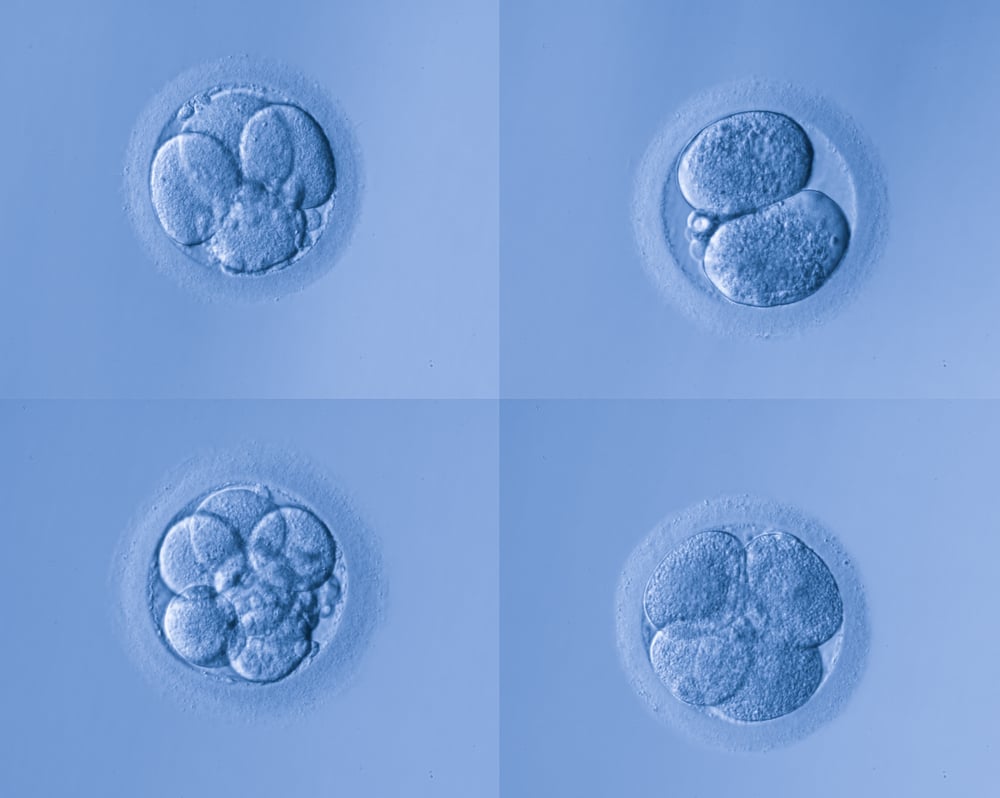

What’s A Gastrula? - BYJU’S NEET

byjus.comembryo zygote blastocyst gastrula stages embryonic embryogenesis fertilization reproduction sexual fetus pregnancy develop formed form byjus

byjus.comembryo zygote blastocyst gastrula stages embryonic embryogenesis fertilization reproduction sexual fetus pregnancy develop formed form byjus